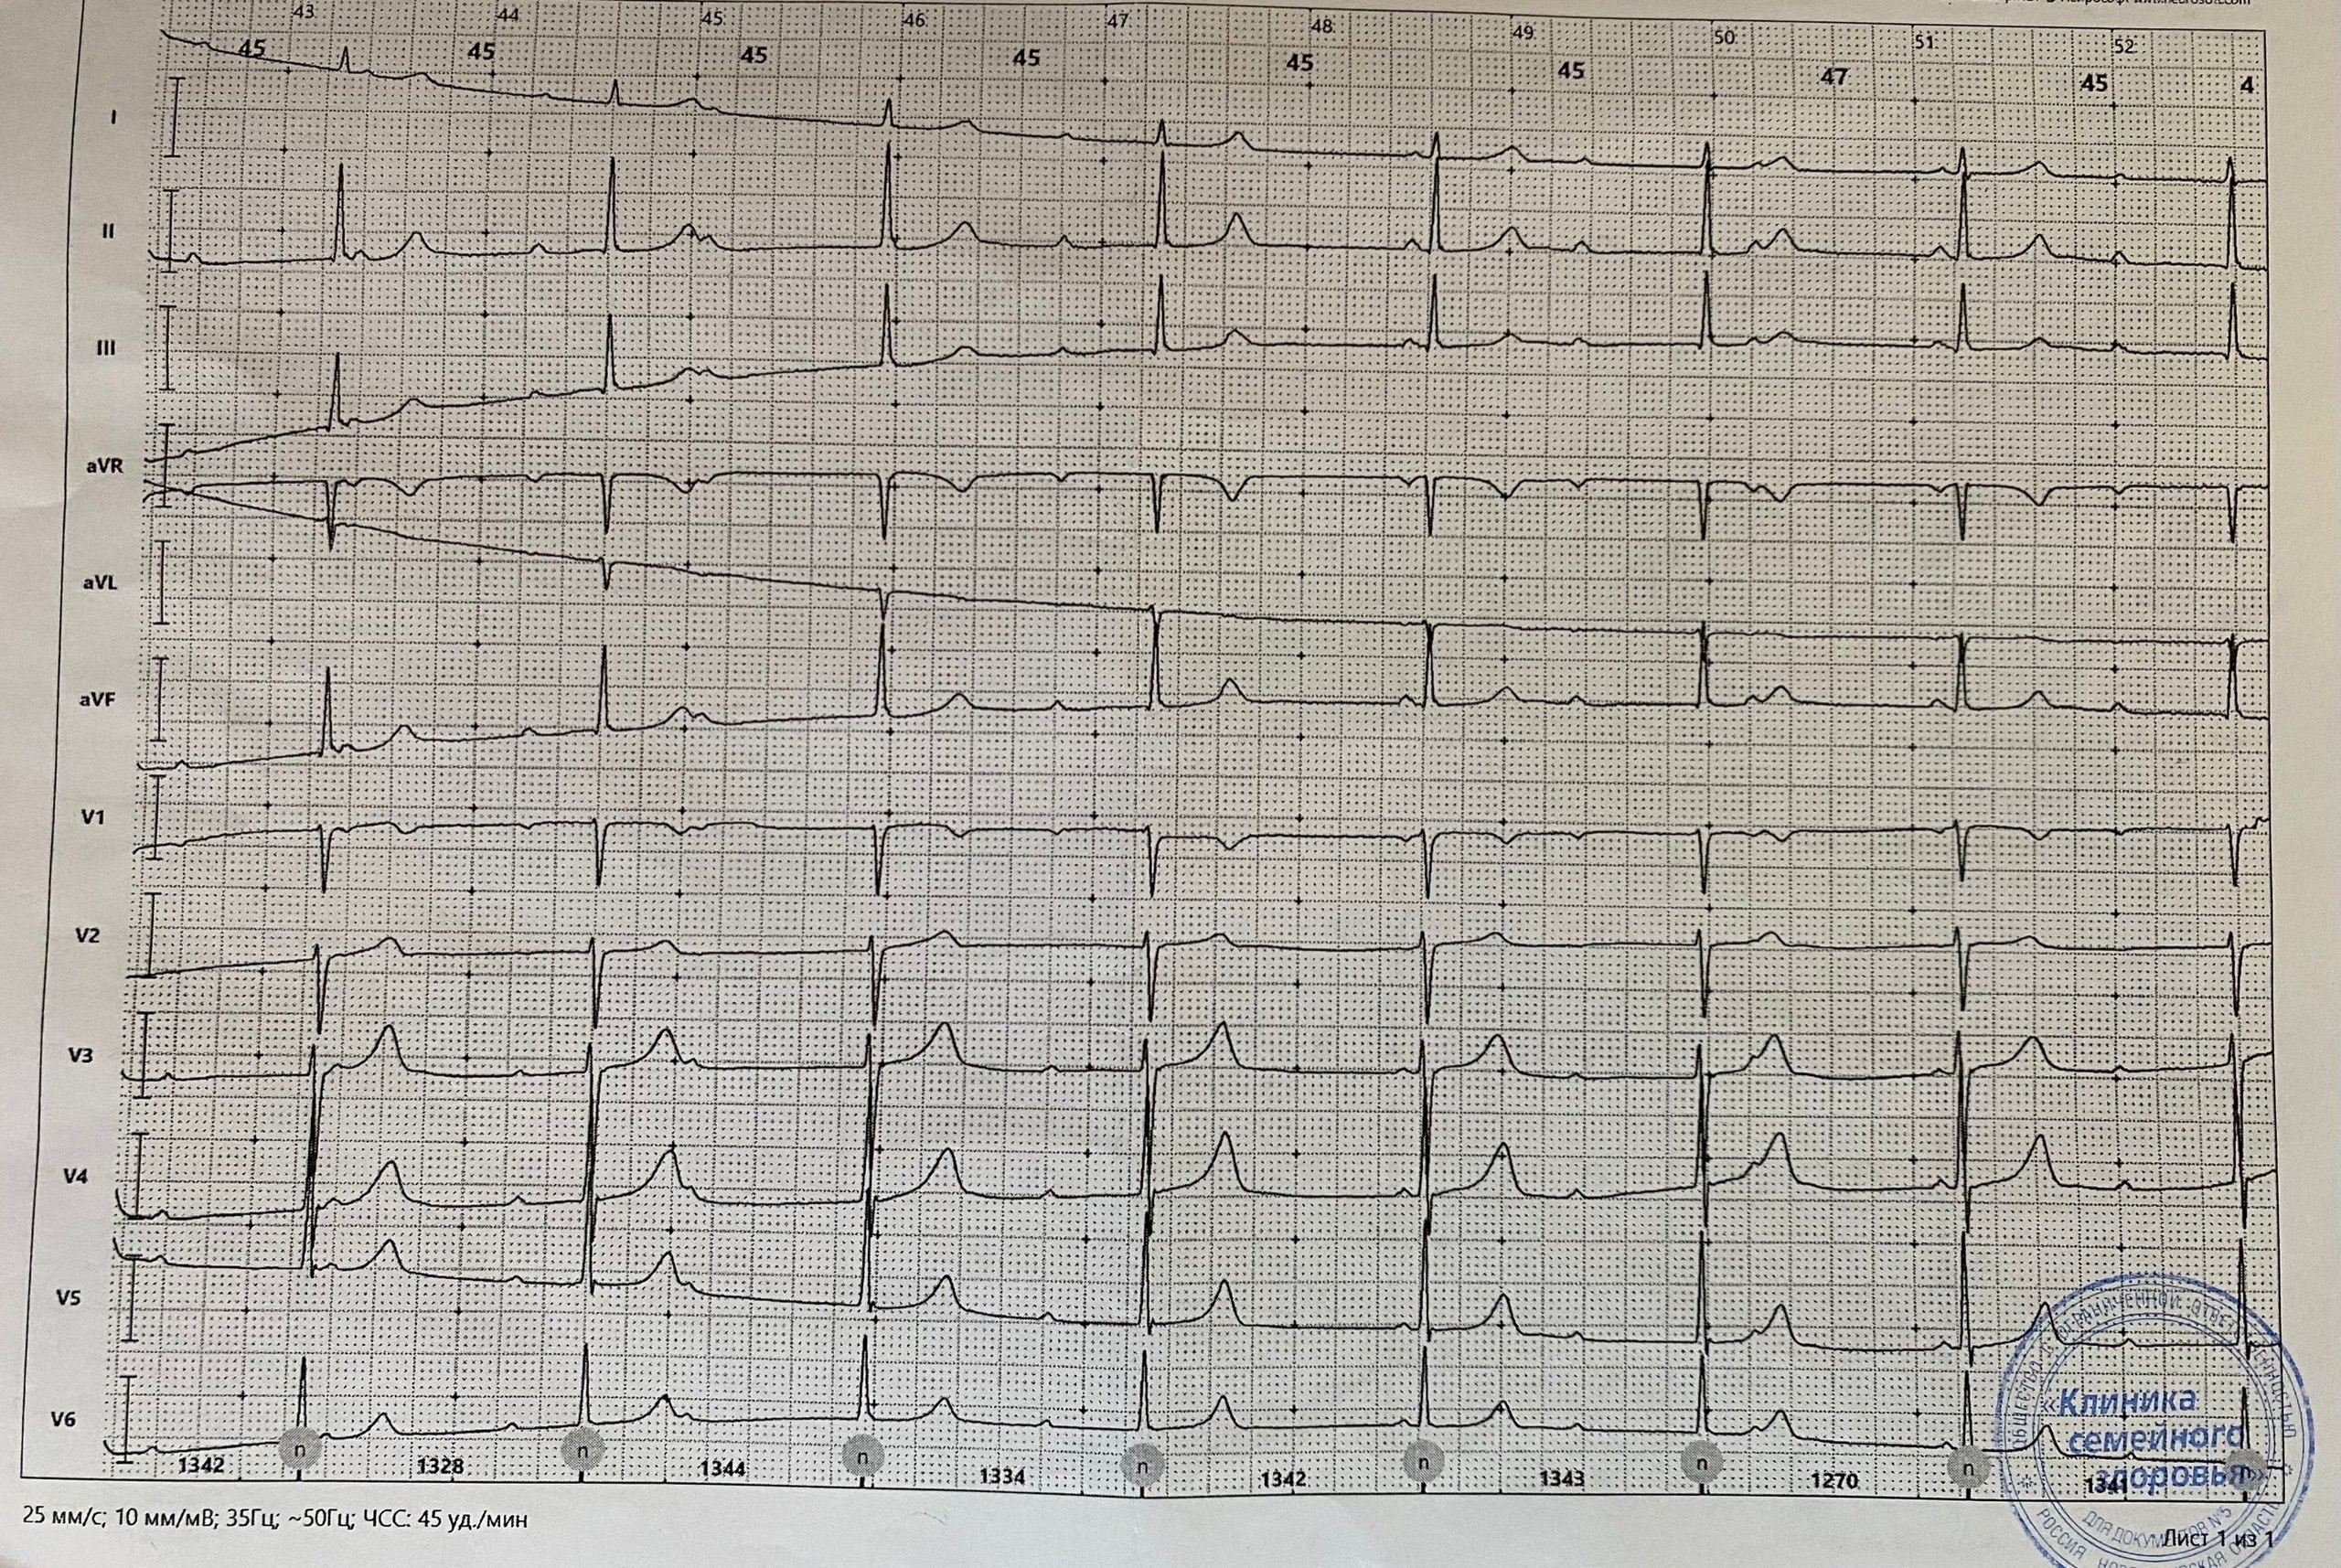

АВ бл 2 тип 2

Обсуждалось здесь https://vk.com/club84409679?w=wall-84409679_13522%2Fall